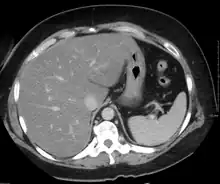

Imaging studies are often obtained during the evaluation process. Ultrasonography reveals a "bright" liver with increased echogenicity. Pocket-sized ultrasound devices might be used as point-of-care screening tools to diagnose liver steatosis. [30] [31] Medical imaging can aid in diagnosis of fatty liver; fatty livers have lower density than spleens on computed tomography (CT), and fat appears bright in T1-weighted magnetic resonance images (MRIs). Magnetic resonance elastography, a variant of magnetic resonance imaging, is investigated as a non-invasive method to diagnose fibrosis progression.[32] Histological diagnosis by liver biopsy is the most accurate measure of fibrosis and liver fat progression as of 2018.[8] Conventional imaging methods, such as ultrasound, CT and MRI, are not specific enough to detect fatty liver disease unless fat occupies at least 30% of the liver volume.[33]